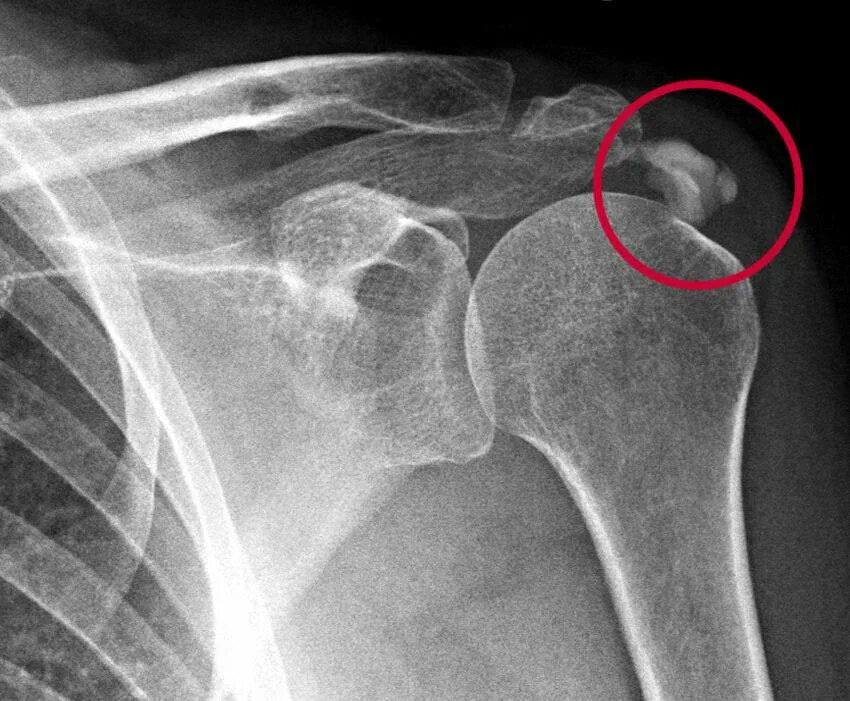

Тендинит сухожилия плечевого сустава